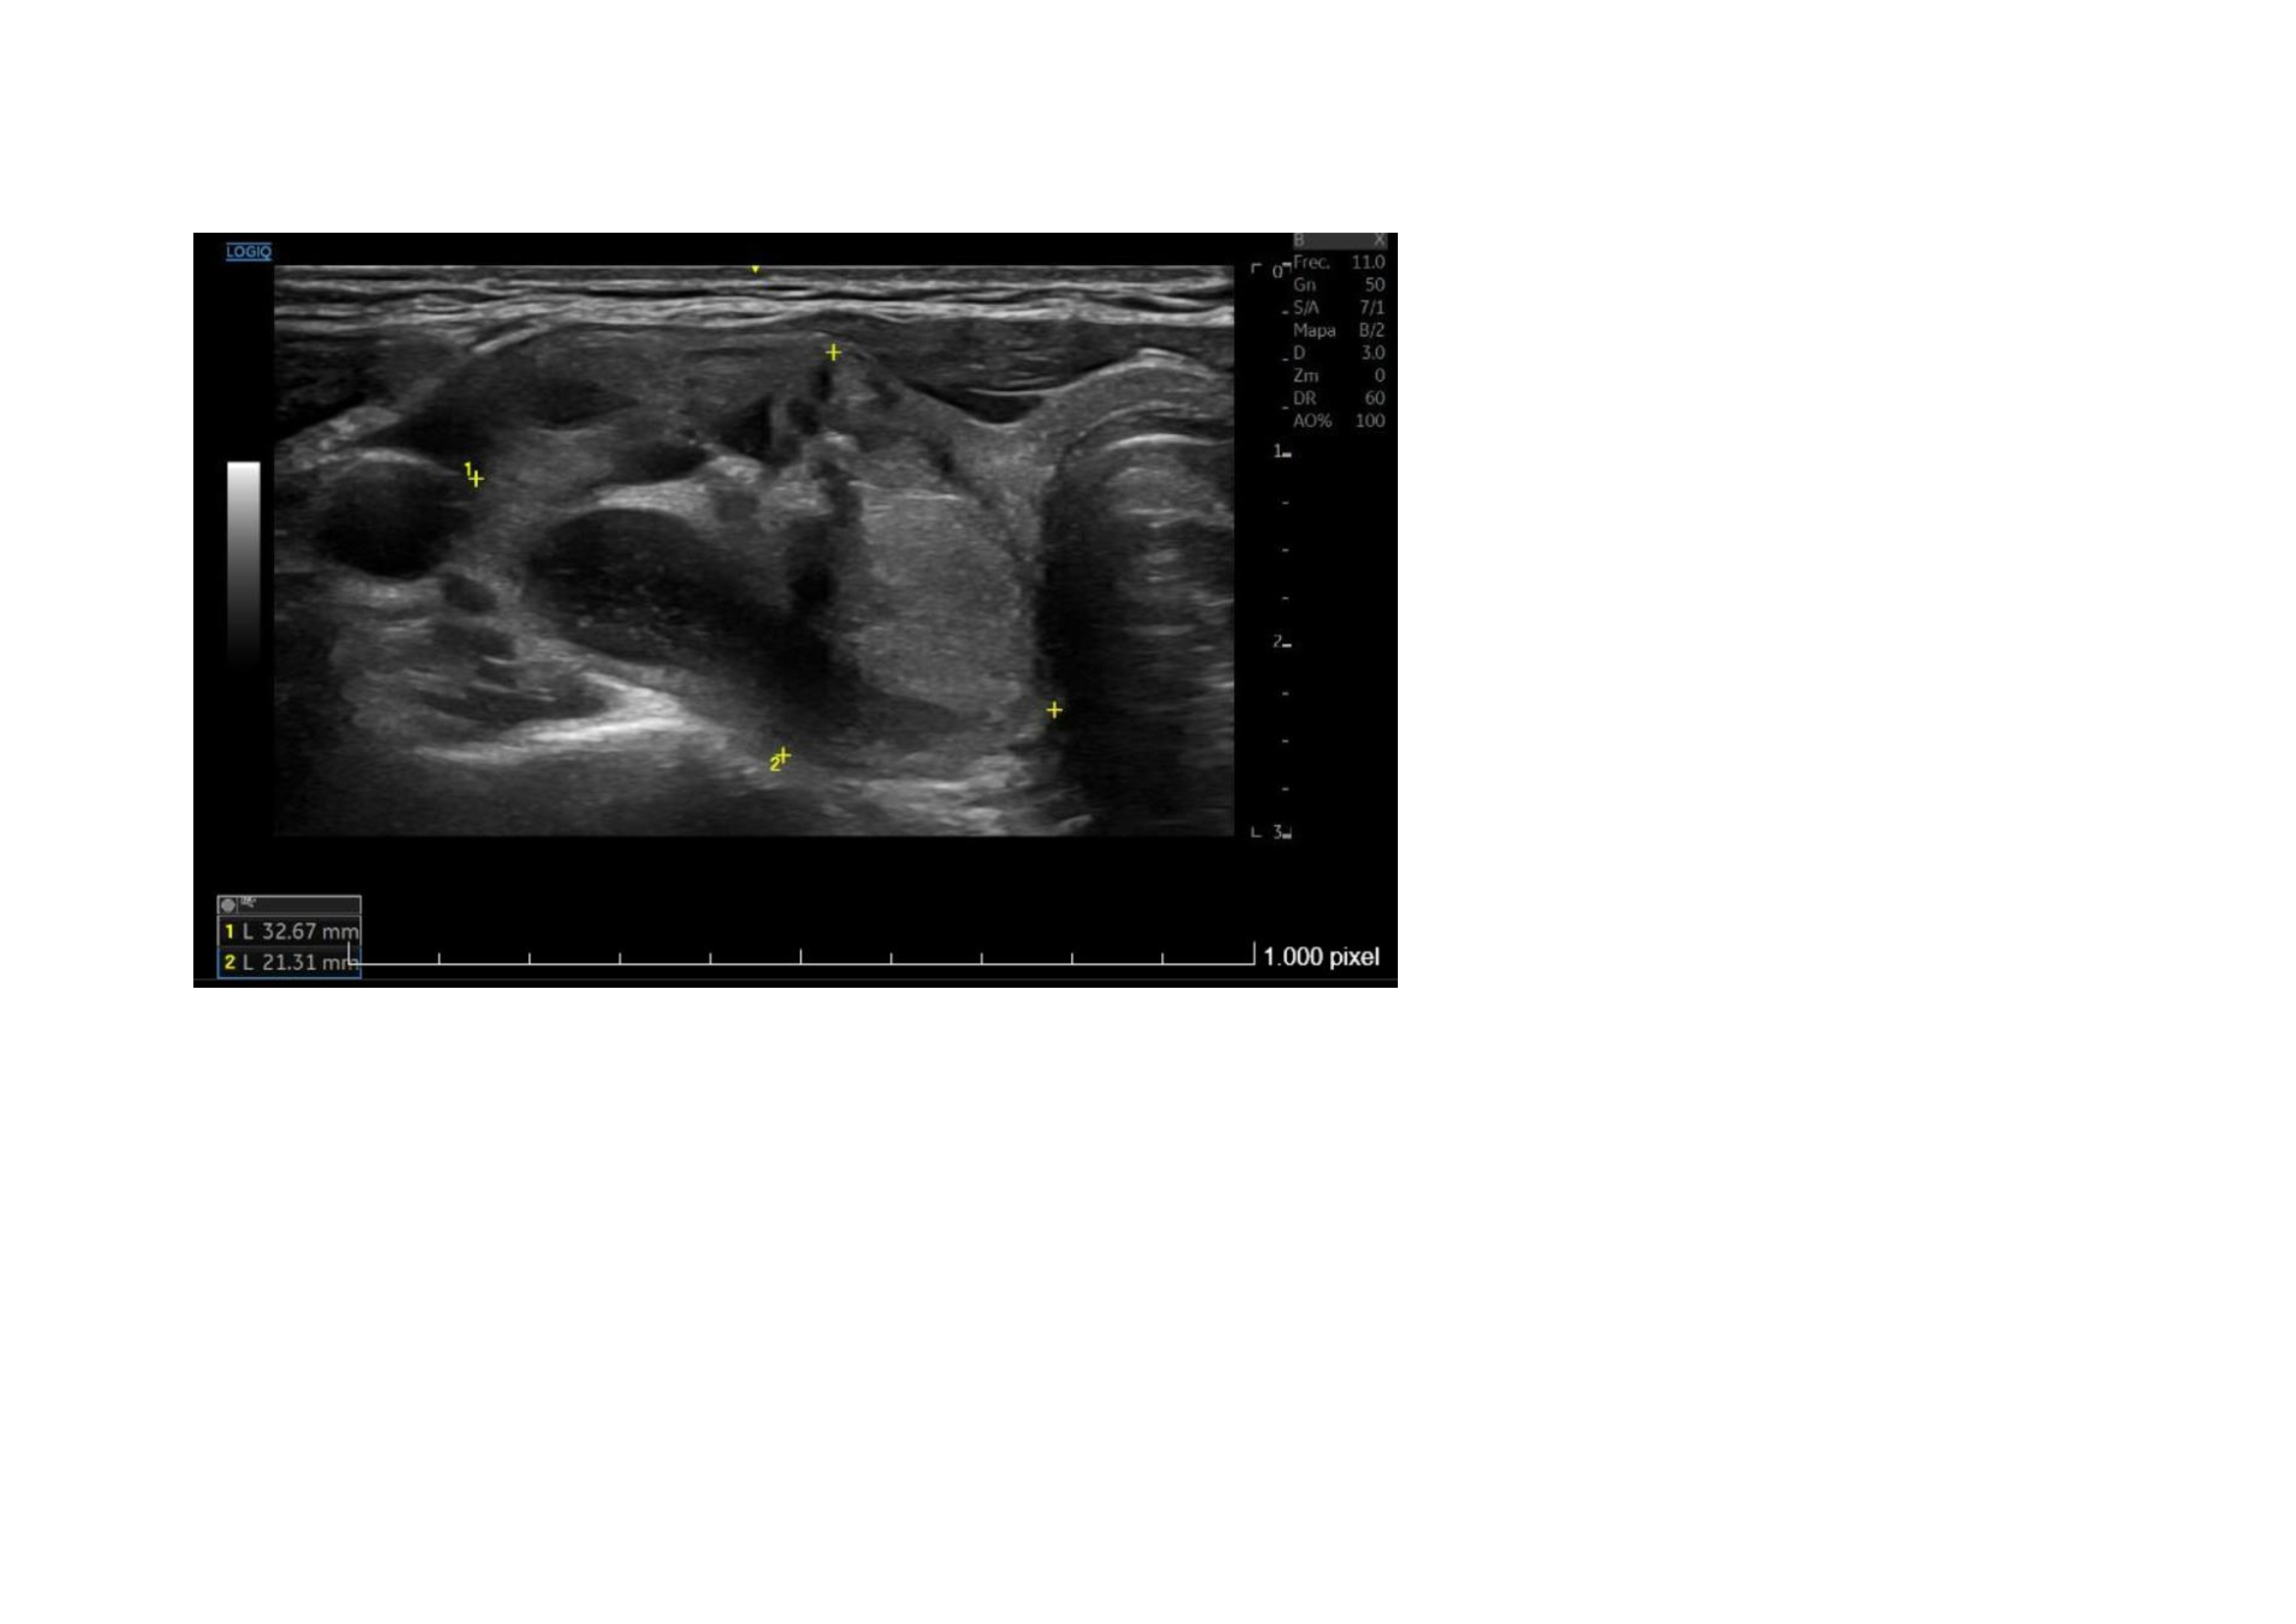

Ecografía Hospital: Lóbulo tiroideo derecho aumentado de tamaño (2,2 cm de diámetro anteroposteior), por la presencia de un nódulo sólido, heterogéneo, levemente hipoecoico, bien definido, con áreas de degeneración quística y calcificaciones groseras en su interior, de 22 x 21 x 33 mm. Resto del tiroides sin alteraciones. No se aprecian adenopatías cervicales. Glándulas salivares sin alteraciones. Conclusión: Nódulo en lóbulo tiroideo derecho, único, TIRADS 4.